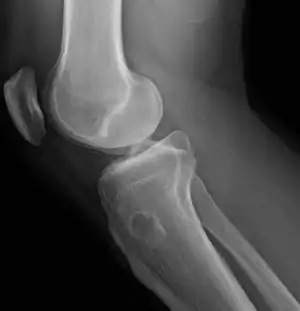

Osteochondroma, a common type of non-cancerous chondrogenic tumors

Diagnosis is made using medical imaging, often when investigating another problem.[3] Tests include X-ray, CT scan, Magnetic resonance imaging and Positron emission tomography.[1] The precise diagnosis is based on histology.[1]

Osteochondroma[2]